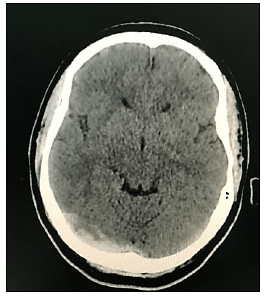

“Paciente, sexo feminino, 40 anos de idade, tabagista ativa, teve quadro de Covid-19 leve há uma semana, evoluindo com cefaleia holocraniana persistente, de forte intensidade, refratária à analgesia simples. Nega ter cefaleia prévia. Após três dias de dor, cursou com um episódio de crise convulsiva generalizada, sendo, então, levada ao hospital de referência próximo a sua residência, onde realizou a seguinte tomografia computadorizada de crânio sem contraste:”

De acordo com as informações, a indicação na tomografia computadorizada de crânio sem contraste se refere ao seguinte sinal radiológico:

Considerando o caso hipotético, qual o diagnóstico da paciente?